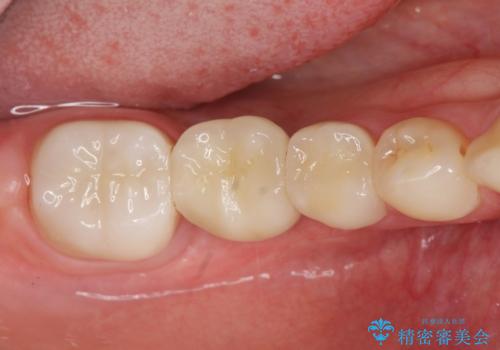

- 上下1本づつの歯を失い、噛めないことの改善を求めて来院されました。

保存可能な歯の虫歯・根管治療を行い、喪失した部分はインプラントを埋入、オールセラミックジルコニアクラウンを製作し審美的に仕上げていきます。

- 120万円(仮歯×6・ファイバーコア×2・ジルコニアクラウン×6・インプラント×2・チタンカスタムアバットメント×2)費用は治療当時の料金となります

今回下顎の欠損部位はブリッジも検討されましたが、並行性の観点から最後方臼歯の神経を取るリスクを抑えるためインプラント治療を選択しました。